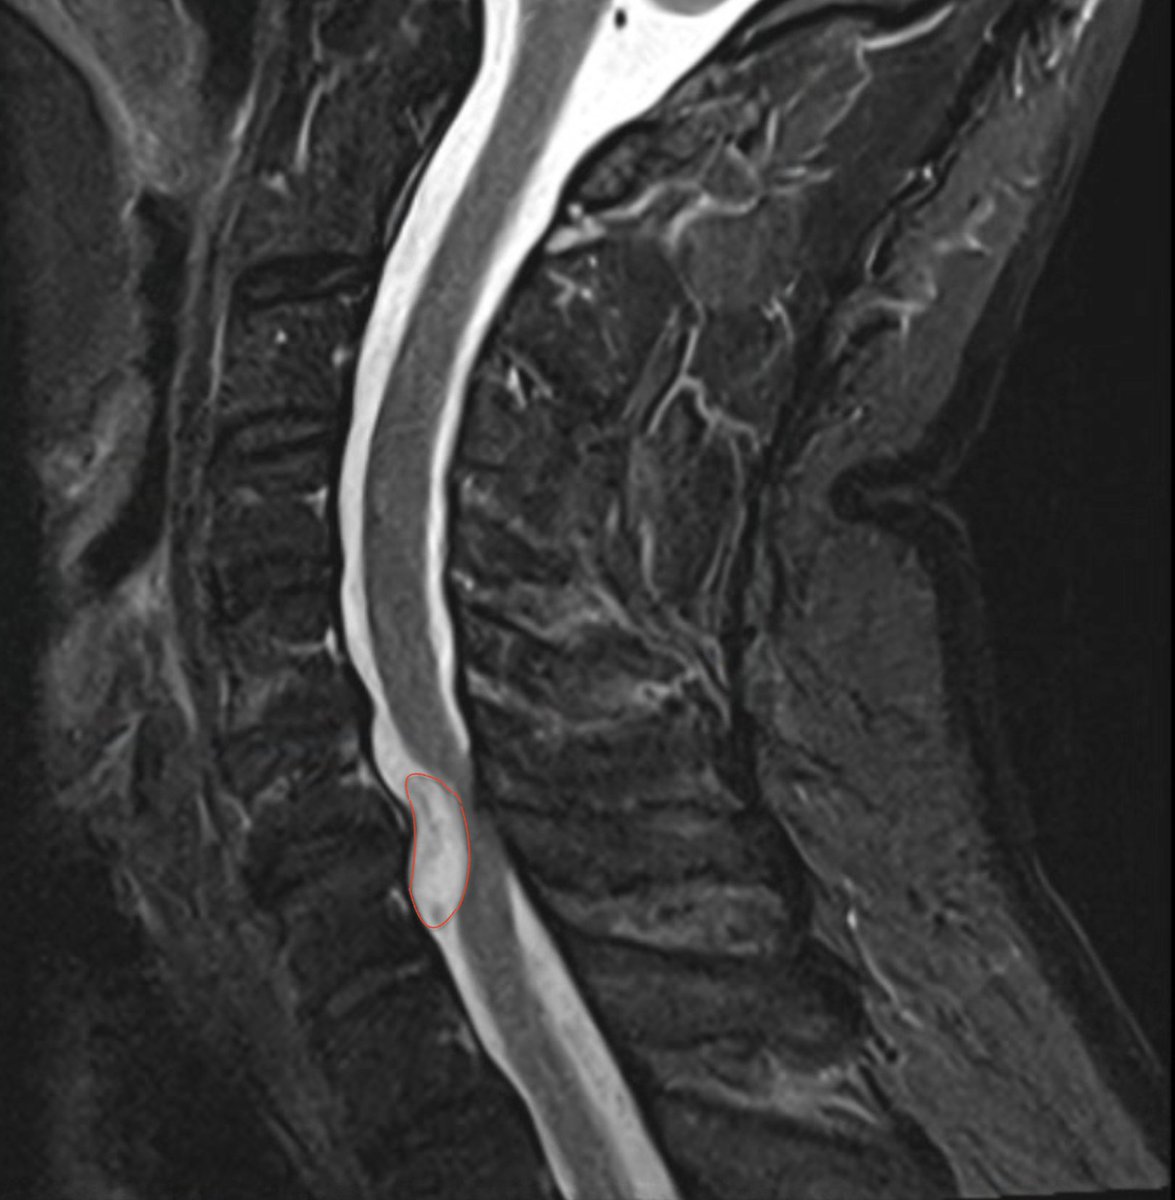

Option 1 - suck it up with pain for next 6 to 9 months and see if body absorbs the lesion.

Option 2 - surgent cuts out spinal disk, removes part of vertibre, and removes lesion. Requires metal plate to fuse C6.

I'm struggling to decide.